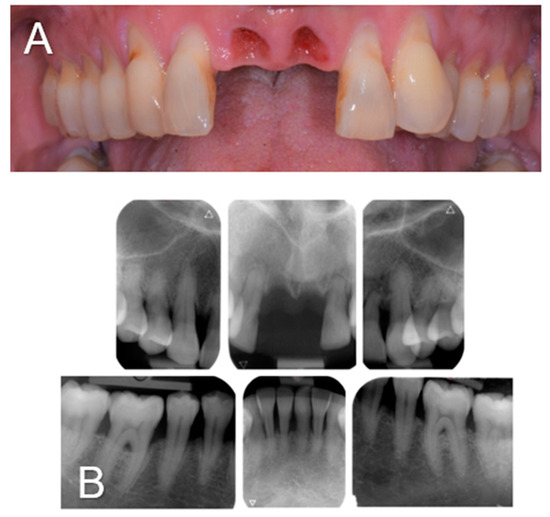

A 61-year-old woman was referred to the Oral Surgery and Implantology Unit of the University Hospitals of Geneva for the treatment of edentulous sites after the dental avulsions of teeth 11 and 21 following traumatic shock due to endotracheal intubation under general anesthesia performed to remove a laryngeal cyst. Past medical history was significant for pharyngeal dysesthesia and a supraglottic cyst. The dental history revealed that the patient had a history of chronic generalized periodontitis treated a few years earlier. Clinical and radiological examination showed generalized bone loss, especially at the edentulous sockets 11 and 21 and adjacent teeth 12 and 22 (Figure 1).

Figure 1.

Clinical view (A) and intra-oral radiographs (B) showing the initial clinical status after dental avulsions due to endotracheal intubation as well as the severe chronic periodontal disease.